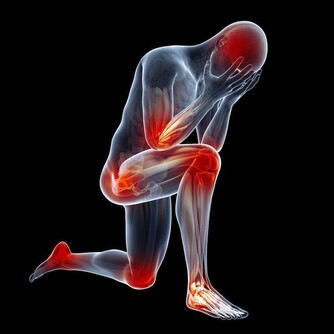

此外還會部分患者會有一些不太常見的症狀,

例如尿痛、射精時感到下體疼痛、尿液或精液中參有血跡、無法正常勃起等。